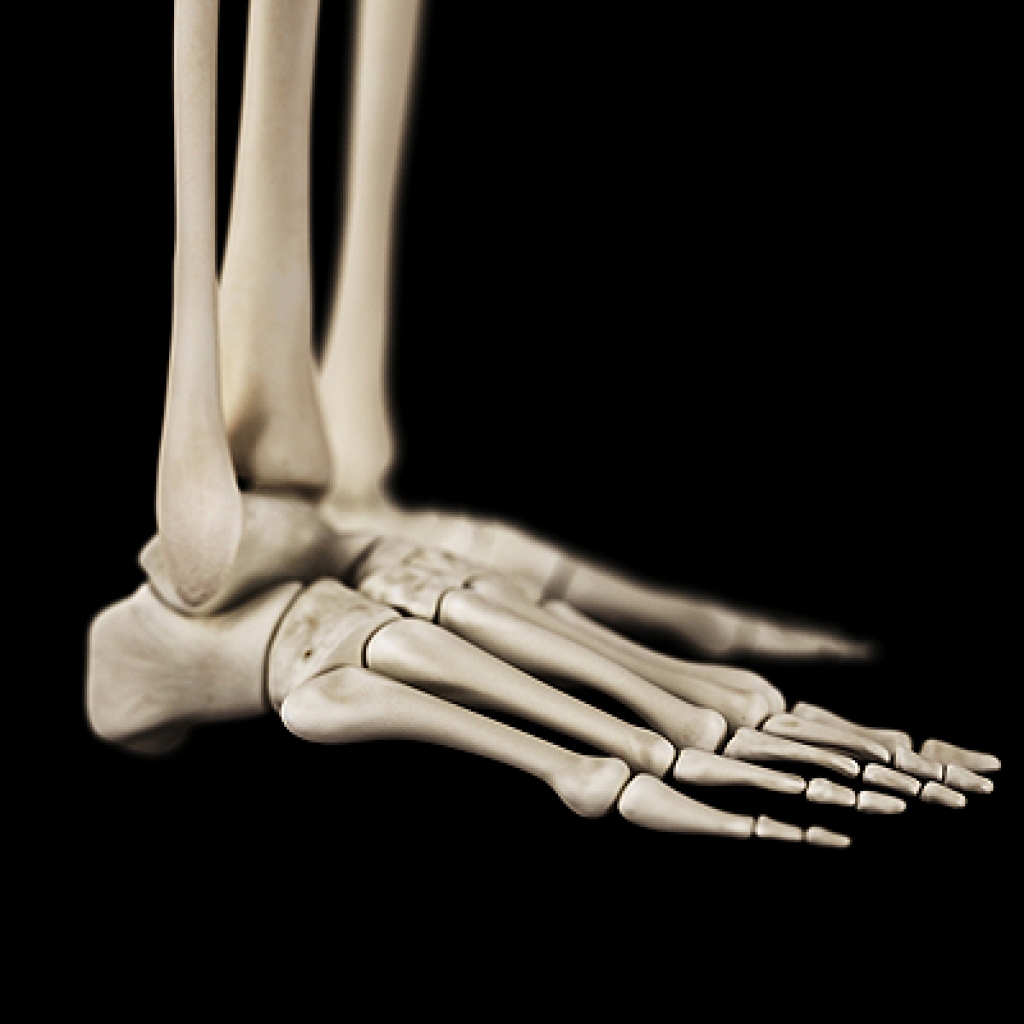

Beneath the skin's surface lies a fascinating framework of foot bones, intricately designed to support our weight and enable movement. Comprising 26 bones, the foot forms three arches that are crucial for balance and shock absorption. However, this intricate structure is vulnerable to various conditions. Fractures can occur due to accidents or stress, while arthritis, an inflammation of joints, can erode bone surfaces. Bunions, caused by misalignment of bones, lead to a bony bump at the base of the big toe. Plantar fasciitis, arising from excessive strain, can cause heel pain. Understanding these conditions empowers us to prioritize foot health. Wearing proper footwear, managing weight, and engaging in a regular exercise routine are vital in preventing foot conditions. If you would like to learn about foot biomechanics, it is suggested that you speak with a podiatrist who can provide you with useful information.

Podiatric biomechanics is a particular sector of specialty podiatry with licensed practitioners who are trained to diagnose and treat conditions affecting the foot, ankle and lower leg. Biomechanics deals with the forces that act against the body, causing an interference with the biological structures. It focuses on the movement of the ankle, the foot and the forces that interact with them.